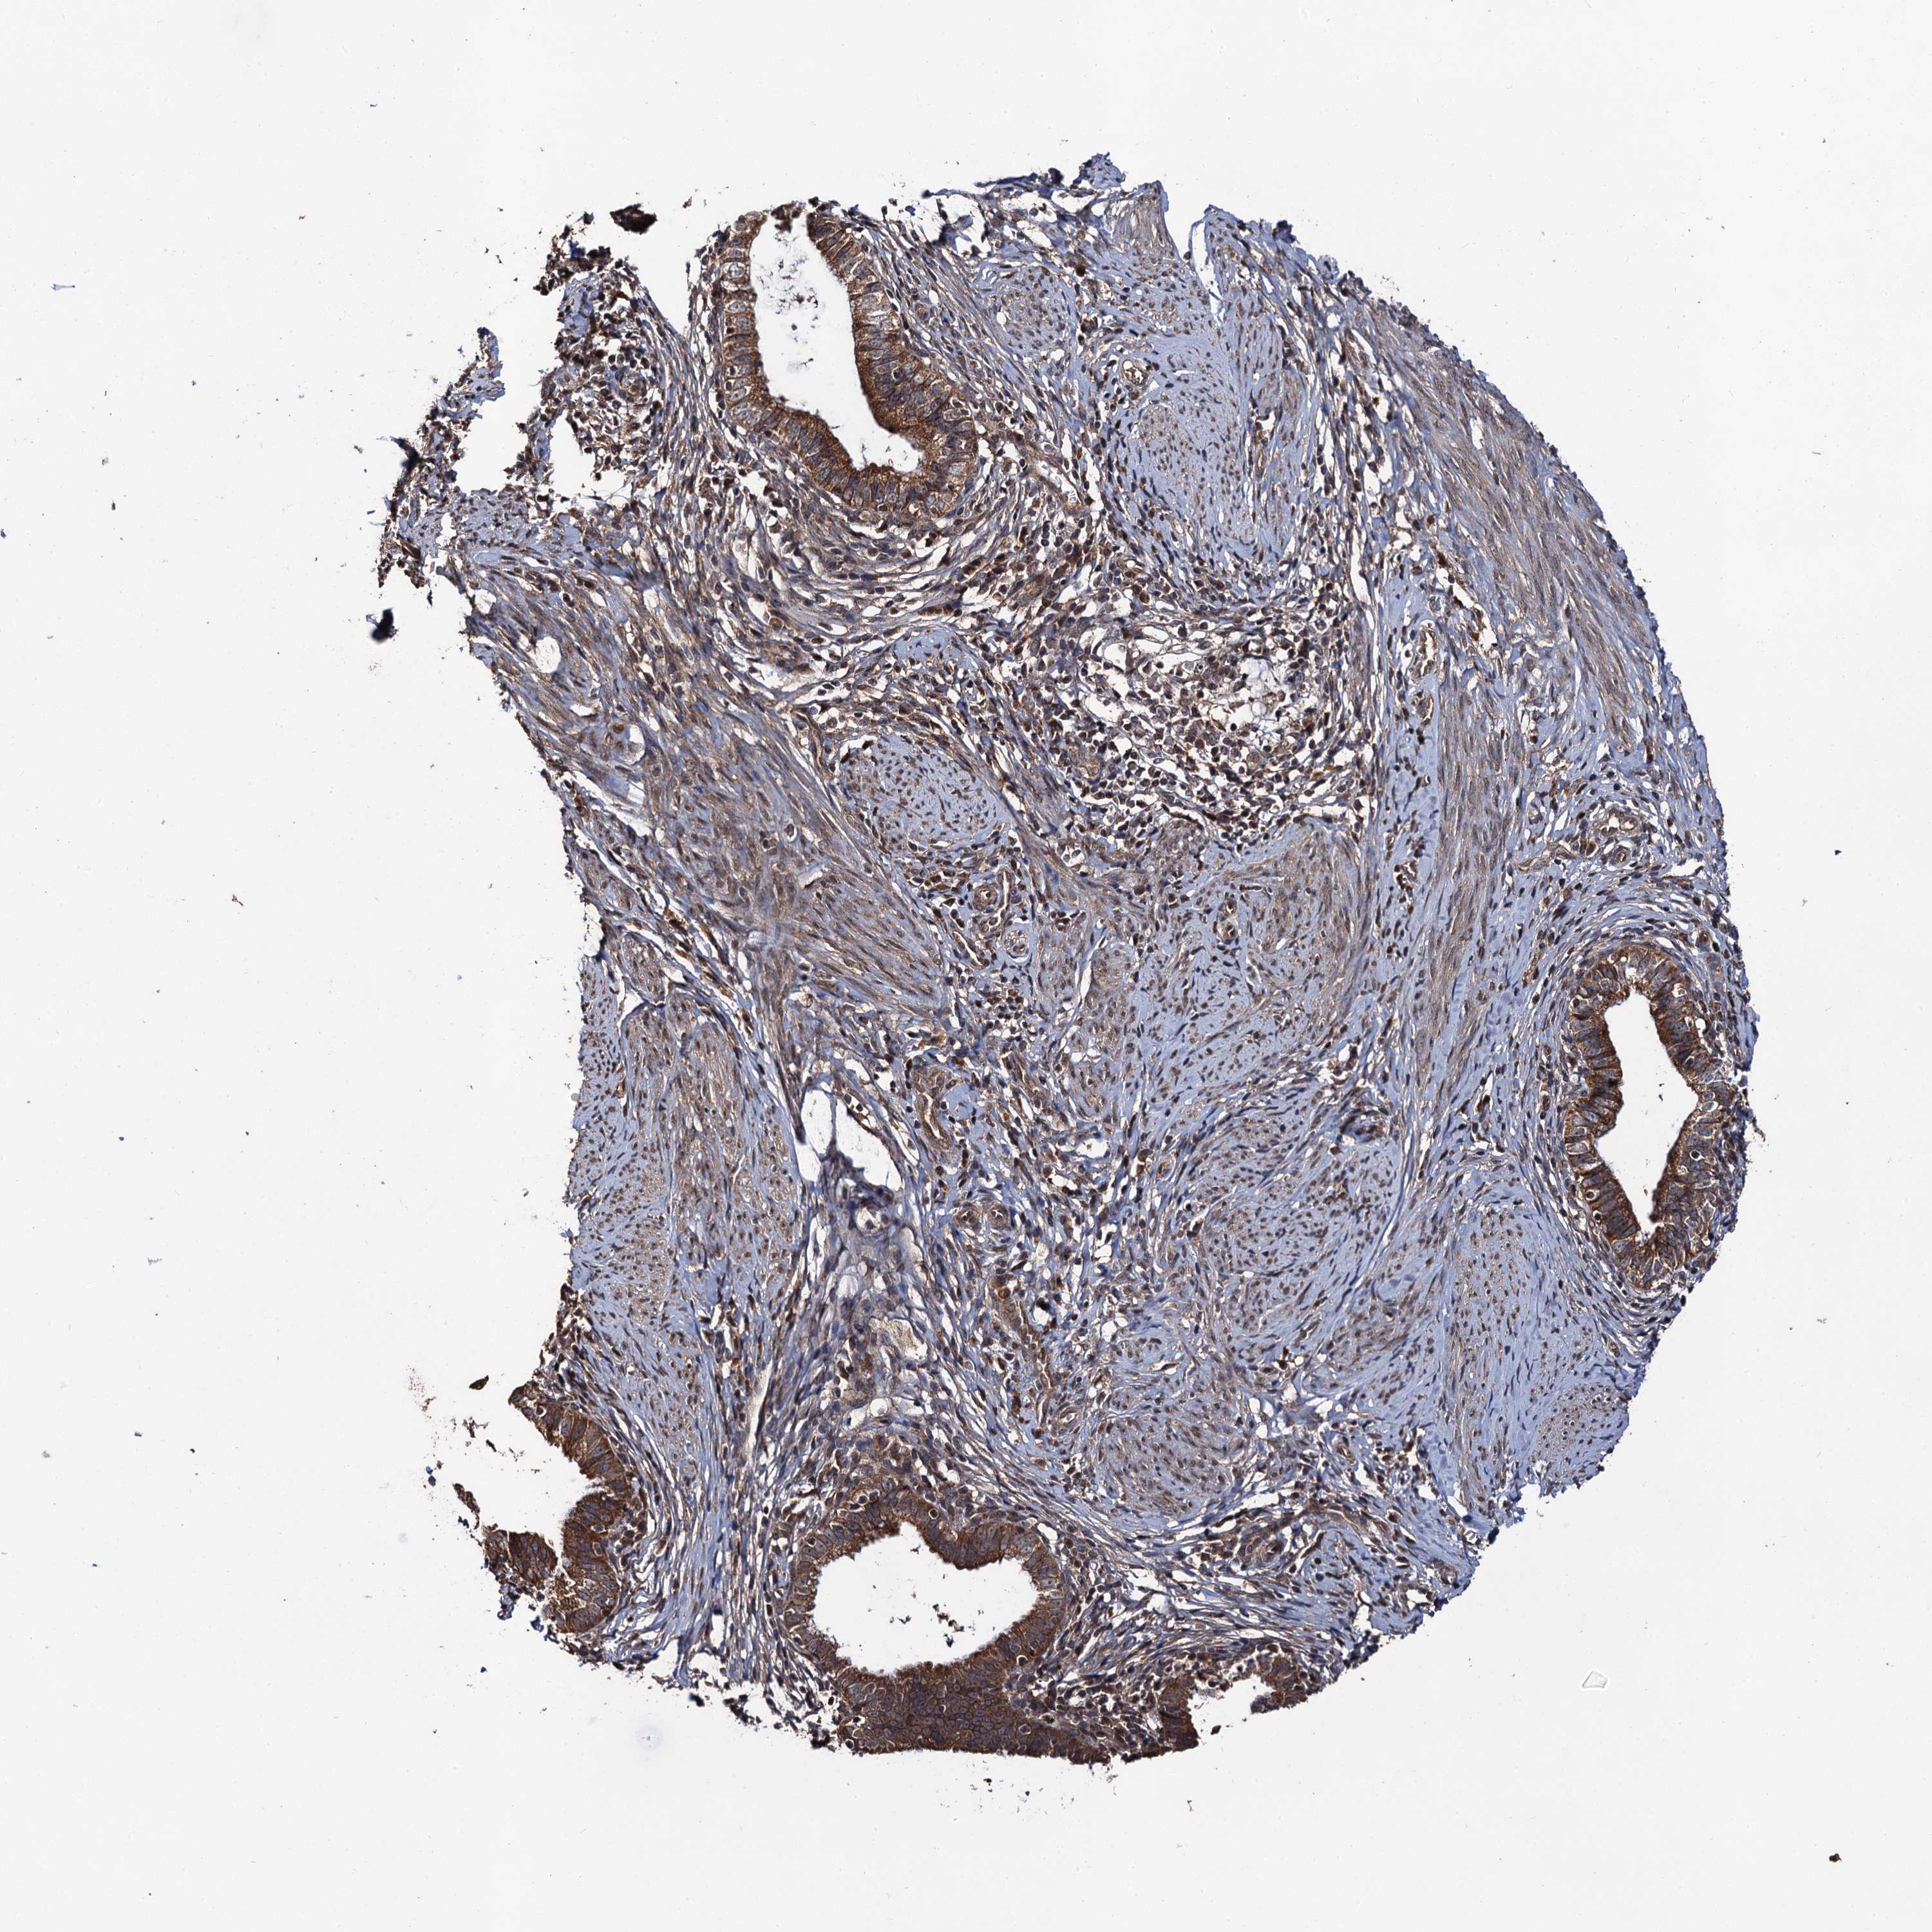

CERVICAL CANCER - Protein expressioni

A mouse-over function shows sample information and annotation data. Click on an image to view it in a full screen mode. Samples can be filtered based on level of antibody staining by selecting one or several of the following categories: high, medium, low and not detected. The assay and annotation is described here.

Note that samples used for immunohistochemistry by the Human Protein Atlas do not correspond to samples in the TCGA dataset.

Antibody stainingi

Antibody staining in the annotated cell types in the current human tissue is reported as not detected, low, medium, or high, based on conventional immunohistochemistry profiling in selected tissues. This score is based on the combination of the staining intensity and fraction of stained cells.

Each image is clickable and will lead to virtual microscopy that enables deeper exploration of all samples and also displays staining intensity scores, fraction scores and subcellular localization as well as patient and tissue information for each sample.

Antibody HPA041439

Squamous cell carcinoma, NOS